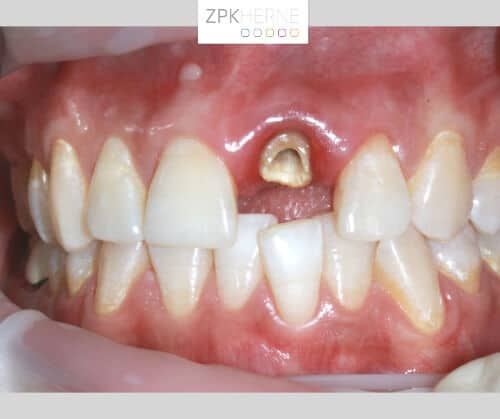

5. Der vorbereitete keramische Aufbau wird aufgesetzt und eine provisorische Krone direkt angepasst. Somit kann die Patientin nach dem Eingriff das Ergebnis direkt sehen und ihr Lächeln ist wieder hergestellt. Die Krone hat keinen Kontakt zur Gegenbezahnung und die Patientin wird angewiesen, in den Wochen nach der OP möglichst keine Belastung auf den Schneidezahn auszuüben.

Gezogener Zahn - Detailansicht

Oberkiefer mit eingeheiltem Implantatkörper

Kieferansicht nach der Implantatbehandlung - Zahn 21